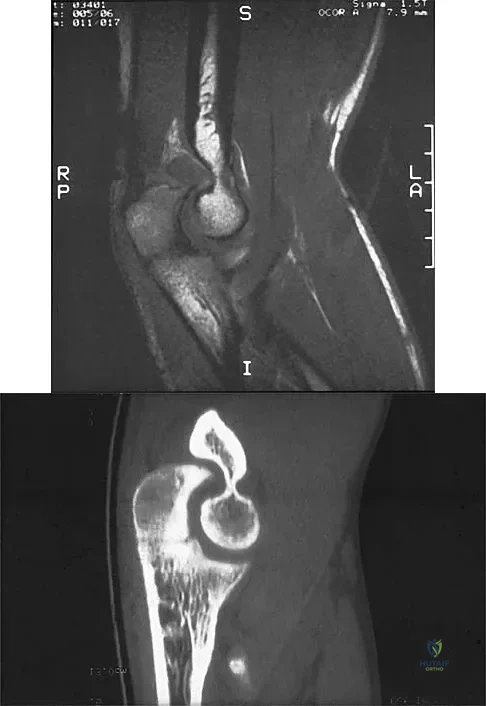

Figure 39 shows the sagittal T1-weighted MRI scan of a 27-year-old man who twisted his knee 2 weeks ago. The arrow is pointing to

Explanation

A right-handed 20-year-old college baseball pitcher has had a 6-month history of vague right elbow pain while pitching. Examination reveals full flexion of the elbow and a loss of only a few degrees of full extension. The elbow is stable, but palpation reveals tenderness over the olecranon. Plain radiographs are inconclusive. MRI and CT scans are shown in Figures 20a and 20b. Management should consist of

Explanation